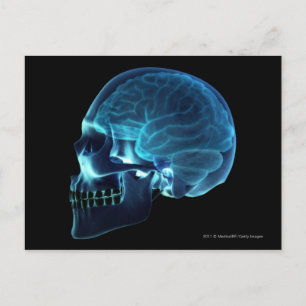

Röntgen från hjärnan inuti en skalle poster

Pris343,00 kr

Röntgen från hjärnan inuti en skalle canvastryck

Pris1 689,00 kr

Röntgen från hjärnan inuti en skalle vykort

Pris21,00 kr